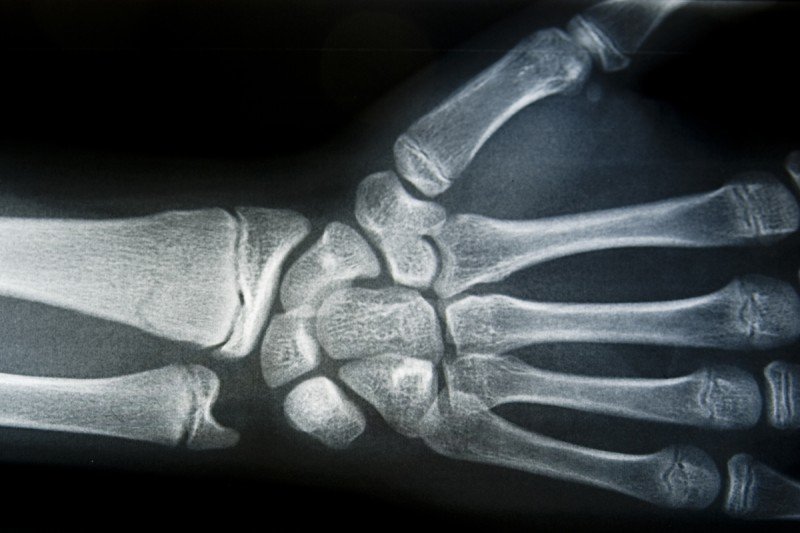

Hand x ray

Hands are complex, which makes operating on tumors incredibly difficult.